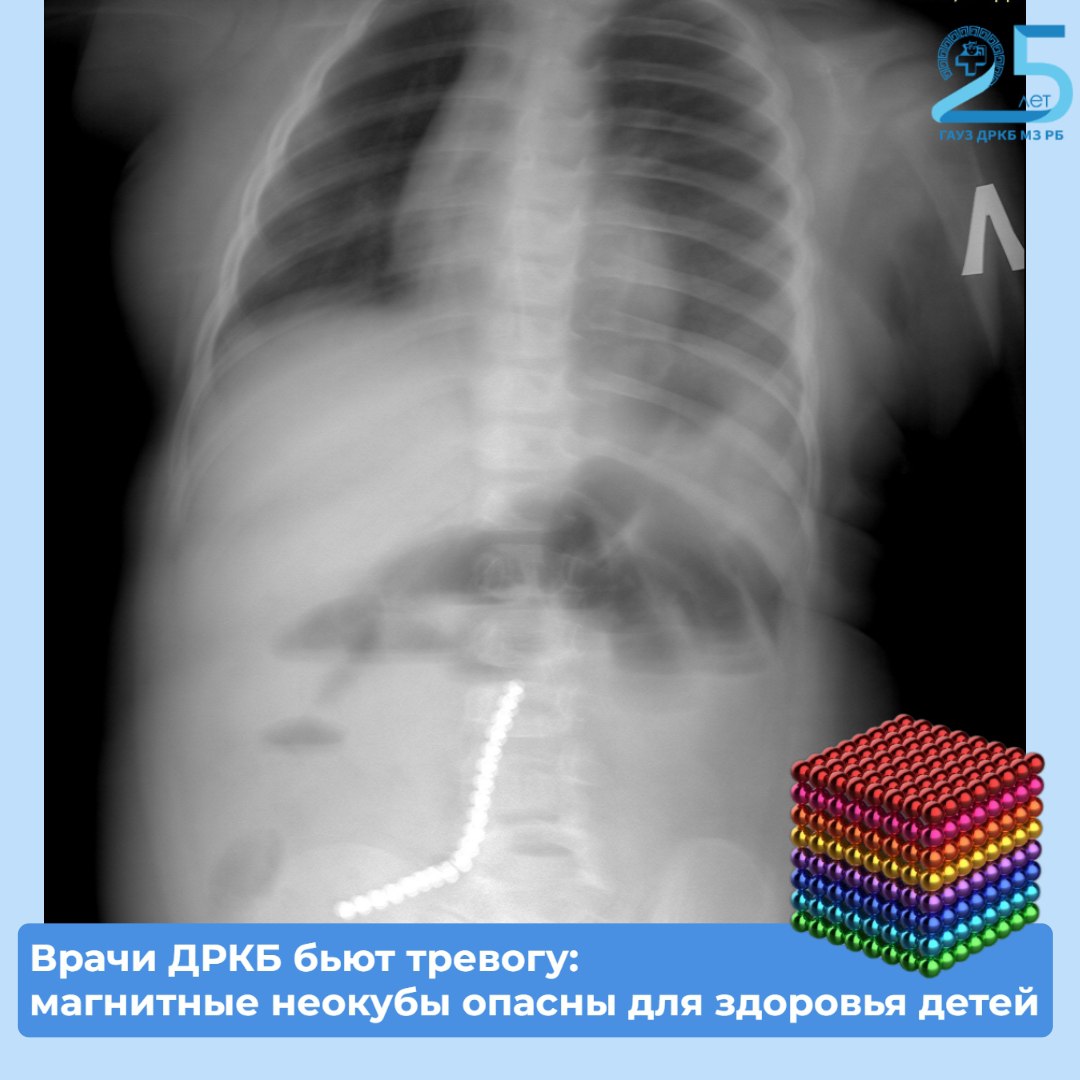

Маленький пациент поступил в больницу с приступами рвоты в тяжелом состоянии. Рентген показал множество инородных тел в желудочно-кишечном тракте. Выяснилось, что несовершеннолетний наглотался магнитных шариков от игрушки.

«Нам удалось удалить девять магнитов эндоскопически (ФГДС). Однако остальные мигрировали по кишечнику, вызвав перфорацию. Петли тонкой, сигмовидной и слепой кишки слиплись между собой из-за магнитного притяжения», — рассказал хирург-эндоскопист ДРКБ Булат Шагдаров.

Хирурги провели открытую операцию, из-за притянувшихся друг к другу магнитов им пришлось удалить поврежденный участок тонкой кишки. Врачи также ушили свищи и извлекли аппендикс, куда опустилась часть магнитов. Сейчас ребенок переведен из реанимации в обычное отделение, его состояние оценивается как стабильное.